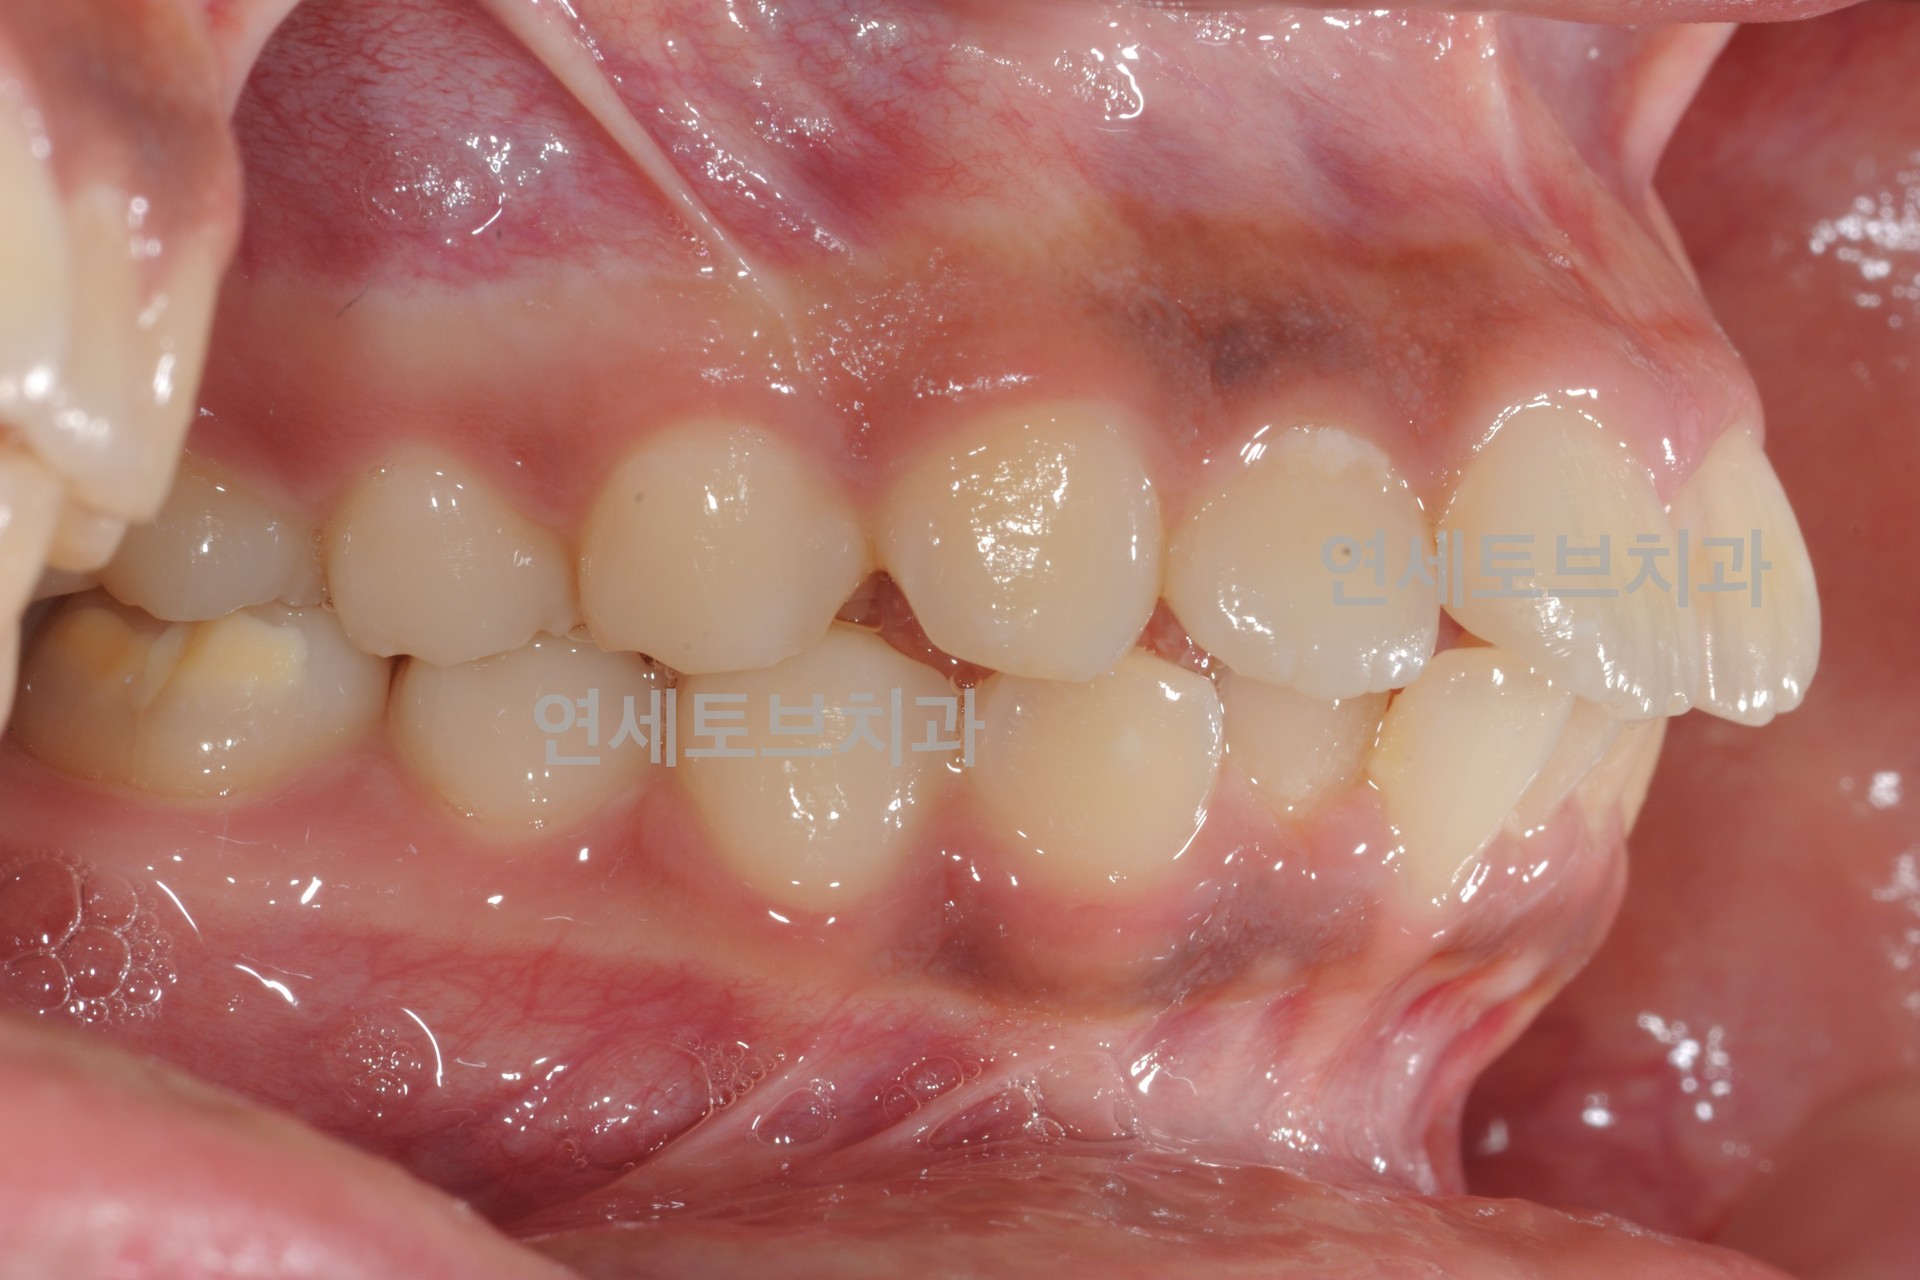

After

돌출입은 윗니나 아랫니(또는 둘 다)가 정상적인 위치보다 앞으로 튀어나온 상태를 말합니다.

이로 인해 입술이 앞으로 돌출되어 보이고, 측면 얼굴 프로필에서 특히 두드러지게 나타납니다.

한국인을 포함한 동양인에게 비교적 흔하게 나타나는 부정교합 유형입니다.